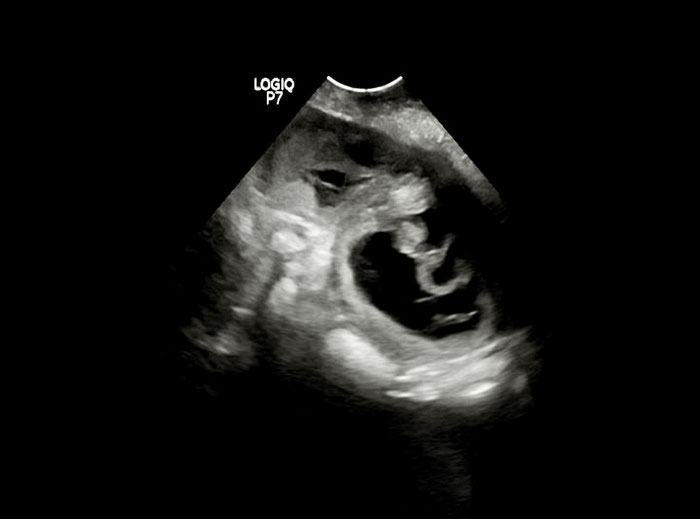

Shani und Mo werden Eltern wir erwarten die Welpen um , den 01.08.2025

Shani und Mo haben am 03.06.2025 Hochzeit gefeiert